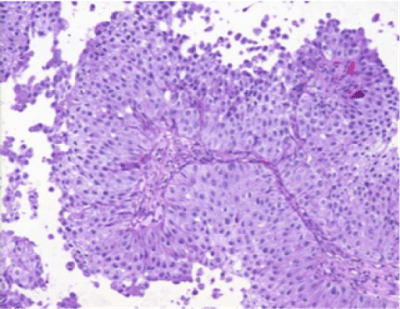

Característicamente, las células del CCT pueden aparecer solas o en pequeños racimos, y presentan grandes núcleos hipercromáticos con cromatina irregular de textura gruesa. Las células malignas identificadas mediante citología pueden clasificarse como:

- Bajo grado: el cual correlaciona con lesiones histológicas de grado I y algunas lesiones de grado II

- Alto grado: se correlaciona con lesiones de grado II, todas las lesiones de grado III, y también con el Carcinoma In Situ.